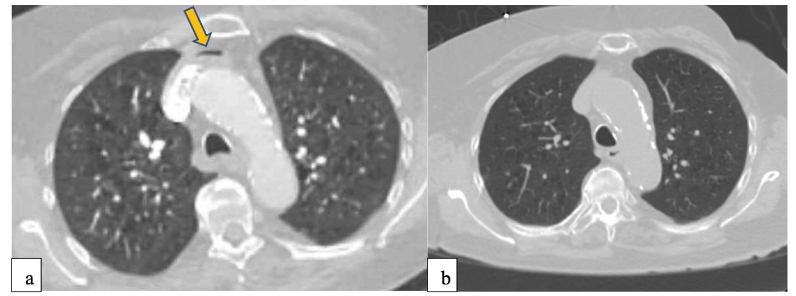

Computed Tomography (CT) and Computed Tomography Pulmonary Angiogram (CTPA) study are not sufficiently sensitive for the detection of small or transient air emboli. They may, however, incidentally reveal large volumes of air in the heart, pulmonary artery, or systemic circulation. Magnetic Resonance Imaging (MRI) is even less sensitive for acute air and not recommended in the setting of emergent diagnosis. They both are useful for identifying complications or excluding alternative diagnoses. Specifically in pediatric populations CT angiography is the preferred modality for detecting pulmonary emboli but has limited use in diagnosing air emboli.

When air embolism is in the early or low volume stages, imaging modalities like CT, CT pulmonary angiogram have low sensitivity for diagnosis of smaller emboli, or distal emboli in the coronary, cerebral or spinal vasculature. Furthermore, emboli may have been dissolved in the circulation by the time CT is done and this may lead to a false negative result. Magnetic Resonance Imaging (MRI) can be more sensitive in detecting cerebral changes but it’s availability and use is less practical in acute settings given long acquisition times. Diffusion weighted (DWI) MRI can help In diagnosis of ischemic injury even when air bubbles are not seen or dissolved.